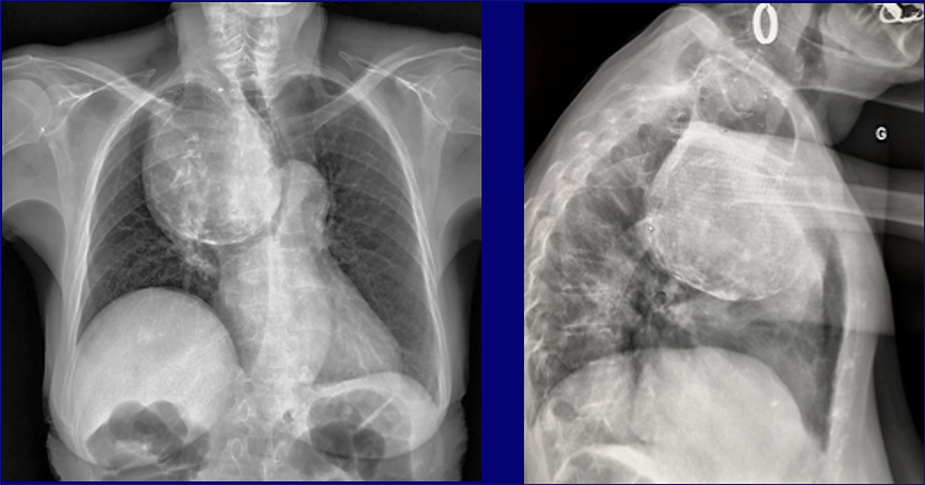

QUIZ N° 007

Patiente de 65 ans

QUEL EST VOTRE DIAGNOSTIC ?

A – GOITRE PLONGEANT

B – TERATOME MEDIASTINAL

C – THYMOME

D – LYMPHOME

E – ANEVRYSME EXCLU DU TABC